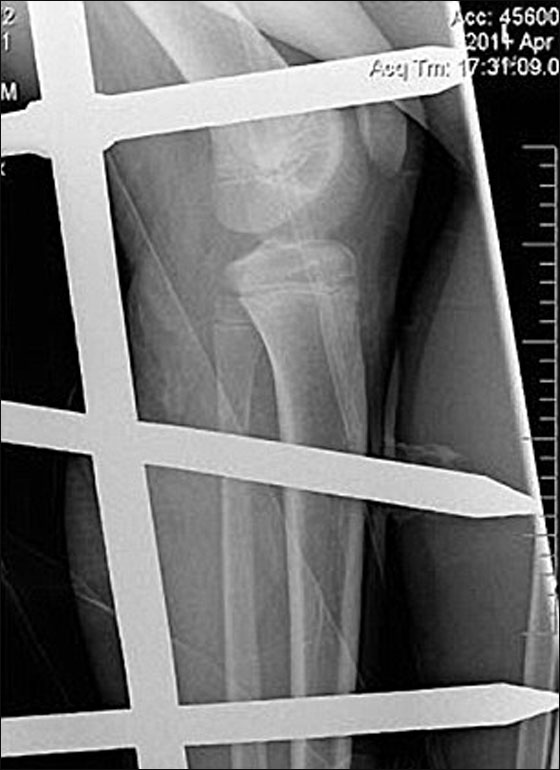

إضطر رجال الاطفاء والانقاذ الى قطع السياج وقصه، لنقل الفتى الى المستشفى، وهنالك، تم تصوير رجله اليسرى بالاشعة والحديد الصدئ ما زال فيها، ثم تم إخضاعه لعملية جراحية لإزالة القضبان من رجله.

من الجدير بالذكر ان الحادثة وقعت في التاسع من نيسان، وبعد مرور شهر، أي اليوم، عاد الفتى الى المدرسة معافى، وفضل والدا بن ان ينشرا صورة الاشعة لرجله، وذلك بهدف تكثيف التوعية للجيل الشاب، بأن يتوخوا الحذر أكثر، وليأخذوا تجربة بن كعبرة، شاكرين الله ان ابنهم نجا من هذه الحادثة الاليمة بأعجوبة.